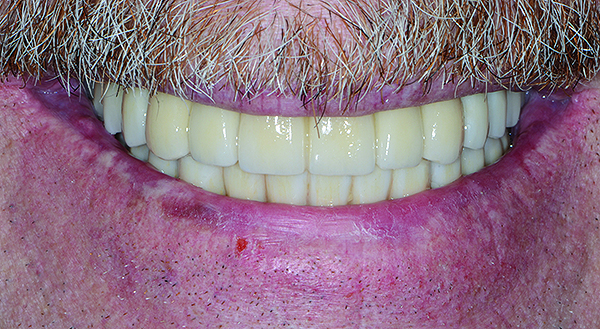

The maxillary prototype was adjusted, polished, and left to function with the mandibular provisional. The definitive maxillary zirconia restoration was then completed from the information provided by the prototype, and the cutbacks for the facial porcelain (Nos. 6 through 11) were done after milling but before sintering. Subsequently, the mandibular prototype was adjusted to the sintered and colored maxillary zirconia framework before the application of porcelain to Nos. 6 through 11 and final glazing (Figure 11). Following this step, the mandibular definitive monolithic zirconia restoration was milled, colored, and sintered. The facial porcelain (Nos. 6 through 11) was applied, and then both maxillary and mandibular restorations were stained and glazed (Figure 12). Both bridges were inserted at the same time (Figure 13 through Figure 15). Minor occlusal adjustments and oral hygiene access was verified and the zirconia surfaces polished. The bridge screws were torqued to 20 Ncm according to the manufacturer’s recommendation, and No. 24 was luted with a provisional cement. Postoperative radiographs were taken (Figure 16).

Fig 15. Intraoral frontal view of completed maxillary and mandibular zirconia restorations.

Figure 15

Fig 17. Intraoral frontal view of maxillary and mandibular zirconia restorations at 1.5 years.

Figure 17